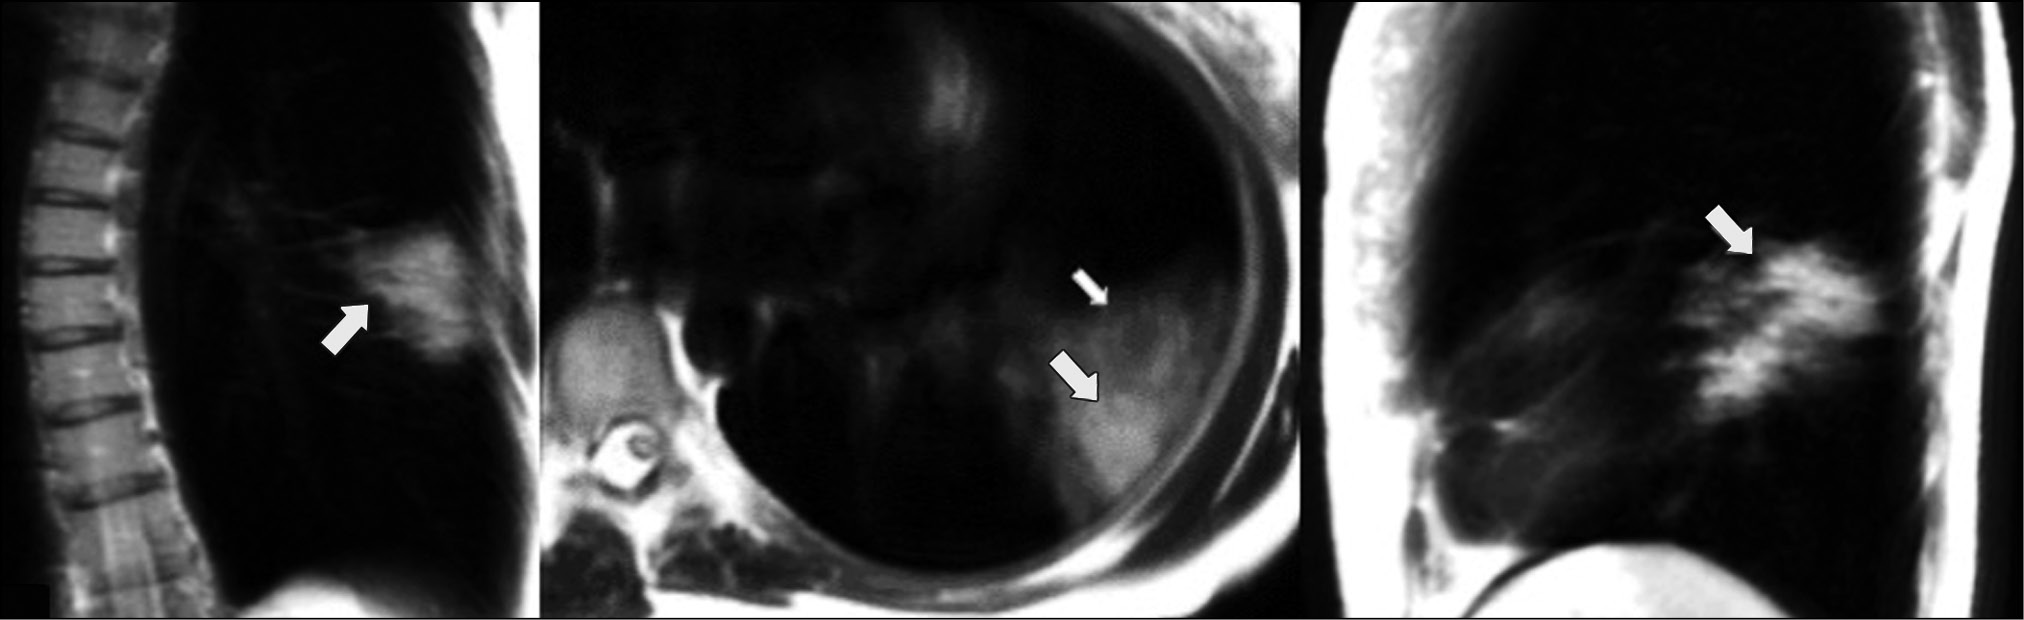

A patient (male, 49 years old) with a mild cough and subfebrile fever up to 37.5°С consulted a doctor on the second day after the onset of symptoms. Dynamic lung MRI showed the predominant “cloudy sky,” which was confirmed by different signal intensities and signal change area sizes depending on the respiratory cycle phase. During inhalation, a weak signal was detected in the lower lobe of the right lung (S6, S9, and S10) in the coronal, axial, and sagittal planes (Fig. 5). Increased signal intensities and area sizes were observed in the coronal and sagittal planes at the end of exhalation (Fig. 6) compared with the areas described. The “cloudy sky” was more prominent in the axial plane during exhalation, whereas the area of visible lung damage was wider.

Figure 5. Dynamic magnetic resonance imaging of the lungs during inhalation in the coronal, axial, and sagittal planes. Arrows point to areas of low-intensity signal with the “cloudy sky” pattern (S6, S9, and S10).

Figure 6. Dynamic magnetic resonance imaging of the lungs during exhalation in the coronal, axial, and sagittal planes. Arrows point to an increase in low-intensity signal areas with the “cloudy sky” pattern (S6, S9, and S10).